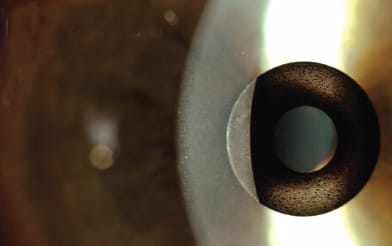

A slit-lamp image of the Flexivue corneal inlay.